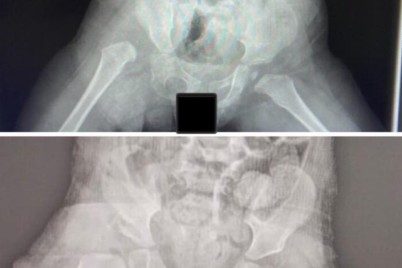

عسير - ندى الشهري في إحدى الحالات النادرة والدقيقة التي أشرف على علاجها استشاري العظام والمفاصل الدكتور محمد لافي العتيبي...

تمكّن – بفضل الله فريق طبي متخصص بجراحة عظام الأطفال بمستشفى الدرعية عضو تجمع الرياض الصحي الثالث ، في...